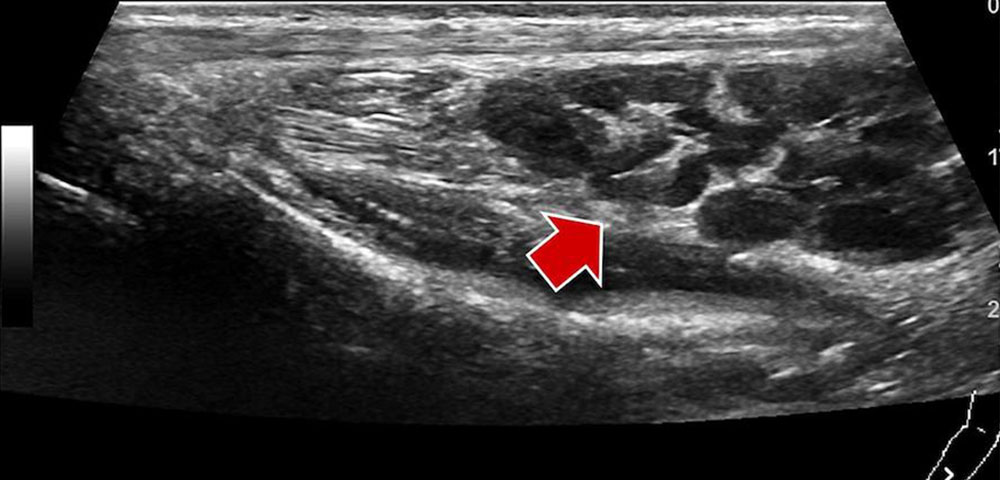

• Venous malformation: In B-mode images, venous malformations are shown as tubular and sponge-like echo-free spaces. Typically, these spaces are surrounded by echogenic fatty tissue. In the absence of thrombi or phleboliths within the venous malformation, the venous malformation is usually easily compressible with the ultrasound probe. Color-coded duplex sonography (CCDS) does not detect increased flow or shows no blood flow within the venous malformation, unlike in fast-flow malformations. The patency of the deep venous system can additionally be assessed by compression ultrasound before and after invasive therapy.

• Lymphatic malformation: In B-mode ultrasound, macrocystic lymphatic malformations appear as echo-free cysts with a thin wall and possibly septa. Blood vessels in the septa and cyst walls are occasionally identifiable. In contrast to venous malformations, macrocystic lymphatic malformations are not as compressible and rather elastic. Microcystic lymphatic malformations show a very heterogeneous ultrasound pattern. In addition to small echo-free microcysts, hypoechoic and hyperechoic masses can also be detected. The cysts themselves do not enhance contrast medium in CEUS. There is no flow on CCDS.